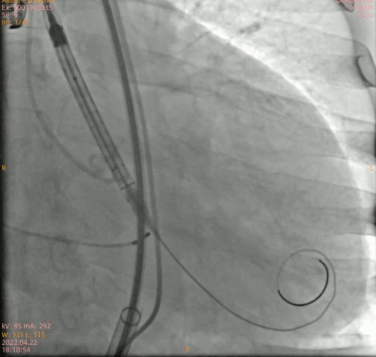

瓣膜三分之二造影

最终形态

术后即刻跨瓣压差测得小于 10 mmHg,手术结果理想。